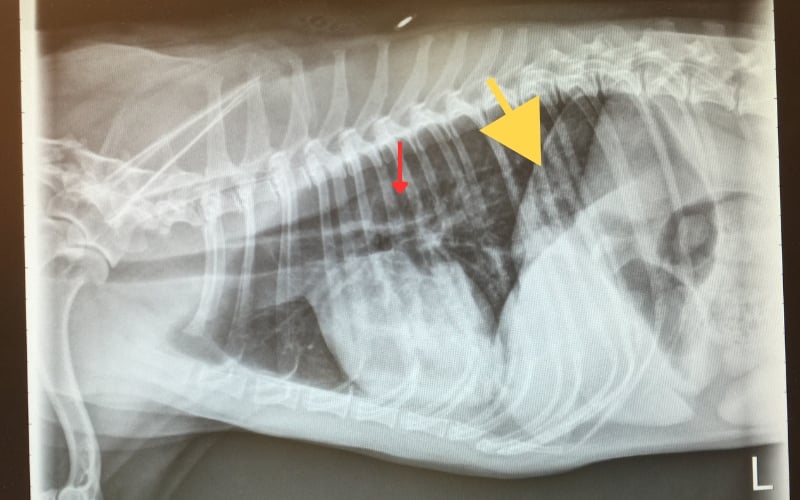

In the X-ray below, the affected lung is lying over the oval-shaped heart, so the pneumonia is difficult to see. The area with the pneumonia appears as bright-white patchy areas over the heart. The small red arrow shows a small dilation of the esophagus.

The wide yellow arrow shows gas in the stomach because Daisy was working so hard to breathe that she was also swallowing extra air. This is common in pets who are struggling to breathe.